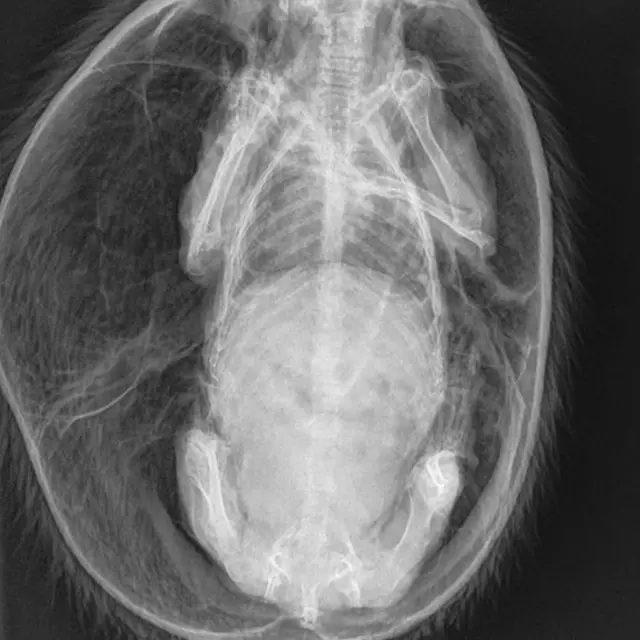

"Я отвезла страдающее животное к ветеринарам в Шеффилд, там ему сделали рентген, выпустили газ, дали антибиотики и обезболивающее. Мы нашли его в критический момент, и я надеюсь, что он выкарабкается", - добавила Дрэнсфилд.

Если газ скапливается под кожей ежа, ее аккуратно протыкают, после чего животное ждет курс медикаментозного лечения.

После операции в Шеффилде самца ежа весом в килограмм перевезли в Центр дикой природы RSPCA в Чешире, где за животным будут наблюдать, давать ему обезболивающее и выпускать из-под кожи воздух до тех пор, пока еж не станет достаточно здоров, чтобы его можно было выпустить обратно на волю.